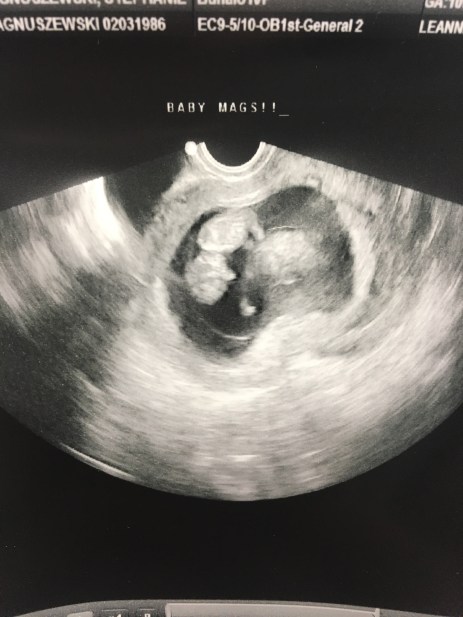

Best moment this week: Had another sonogram today. This is the one I have been waiting for. My nerves have been on edge trying to get through week 6 and thankfully everything looked great! She had nothing bad to report, we saw a little flickering heart beat at 159 bpm and the crown to rump measurements were exactly on point with 7 weeks 5 days.

Here was our second sonogram at 7 weeks 5 days. A little bigger then 2 weeks ago!!